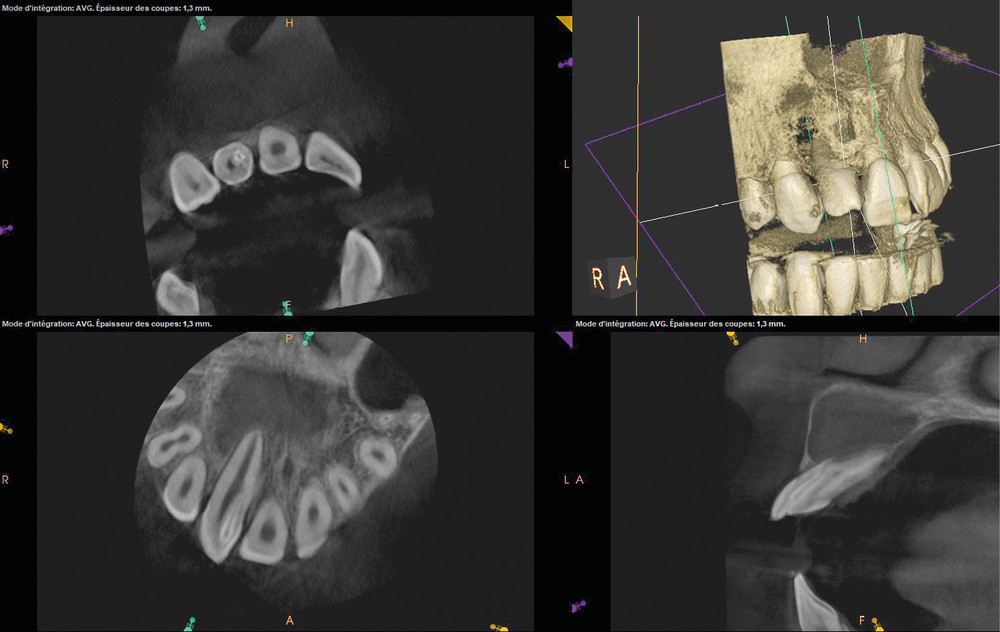

La patiente, âgée de 12 ans, s’est présentée à ma consultation avec une demande du chirurgien de réaliser le traitement endodontique de la 12 avant le curetage sous anesthésie générale. La radiographie périapicale préopératoire a mis en évidence une anatomie complexe. Les tests préopératoires ont montré un sondage parodontal sain, une percussion positive et un test au froid positif. La patiente présentait également une fistule vestibulaire active. Le Cone Beam a mis en évidence la présence d’une dens in dente et d’une lésion imposante ainsi qu’une palatoversion importante de la racine de la 12. La lésion est-elle responsable de ce mouvement dentaire ? (fig. 1, 2 et 3).